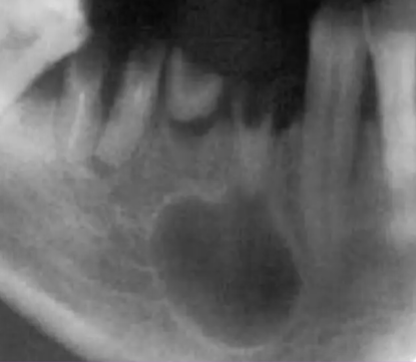

Describe this Radicular Cyst

Epicenter at apex (usually evidence of dental disease or trauma)

Well-defined, corticated

Lucent

Circular

Resorption, Displacement, Expansion (effect on adjacent structures)

Why is this Radicular cyst less circular/oval in this case?